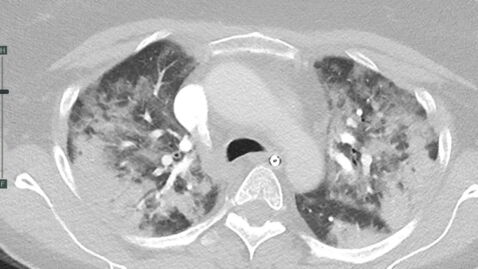

But a second bird's eye perspective of a set of lungs that were affected by the coronavirus under a CAT scan will show the complete opposite of what they should normally look like. College member Associate Professor Stefan Heinz explains that:

More under this adMore under this adThe lungs in the patient who has Covid are all white and full of inflammatory cells and virus and abnormal cells. When it gets as bad as the one in the, in the CAT scan they can end up needing to have mechanical ventilation so you really have to pump the air in through an endotracheal tube.

And added:

That's why he's got these tubes, that's the ETT or the endotracheal tube, that's where you have an operation that just goes down into your trachea and then mechanically ventilates you and that allows them to get a lot more oxygen to the parts of the lungs that are working.More under this adMore under this ad

Though Dr. Heinz explains that the second image is that of an extreme example, people who have recovered from the virus have shown scarring in the lungs weeks and months post exposure. He also explained that the only way to avoid this from happening is protecting oneself with vaccines as it has been proven to dramatically reduce cases requiring intensive hospitalisation.